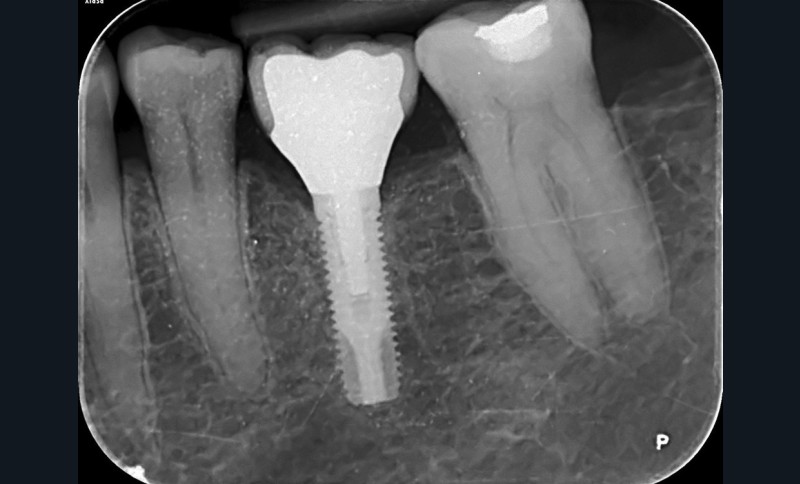

– la péri-implantite définie comme une inflammation des tissus mous péri-implantaires avec une destruction irréversible de l’os péri-implantaire (fig. 2a-b).